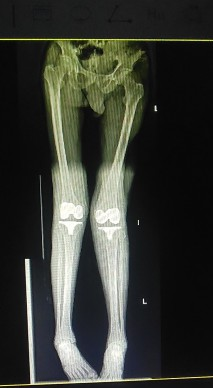

术前可见膝关节过伸畸形、关节外翻不稳定,术前DR显示左膝关节明显外翻畸形

张勇华副院长、骨科二区副主任易治国及骨科团队经充分讨论分析,诊断:双侧全膝关节置换术后假体松动,需行翻修手术,因考虑患者高龄对手术耐受情况及双膝严重程度计划分两次手术完成,先将严重的左侧手术。经充分的术前准备,患者左膝关节置换翻修手术顺利,经过医护人员的精心治疗和康复护理指导,住院期间已在助行器辅助下站立、行走。